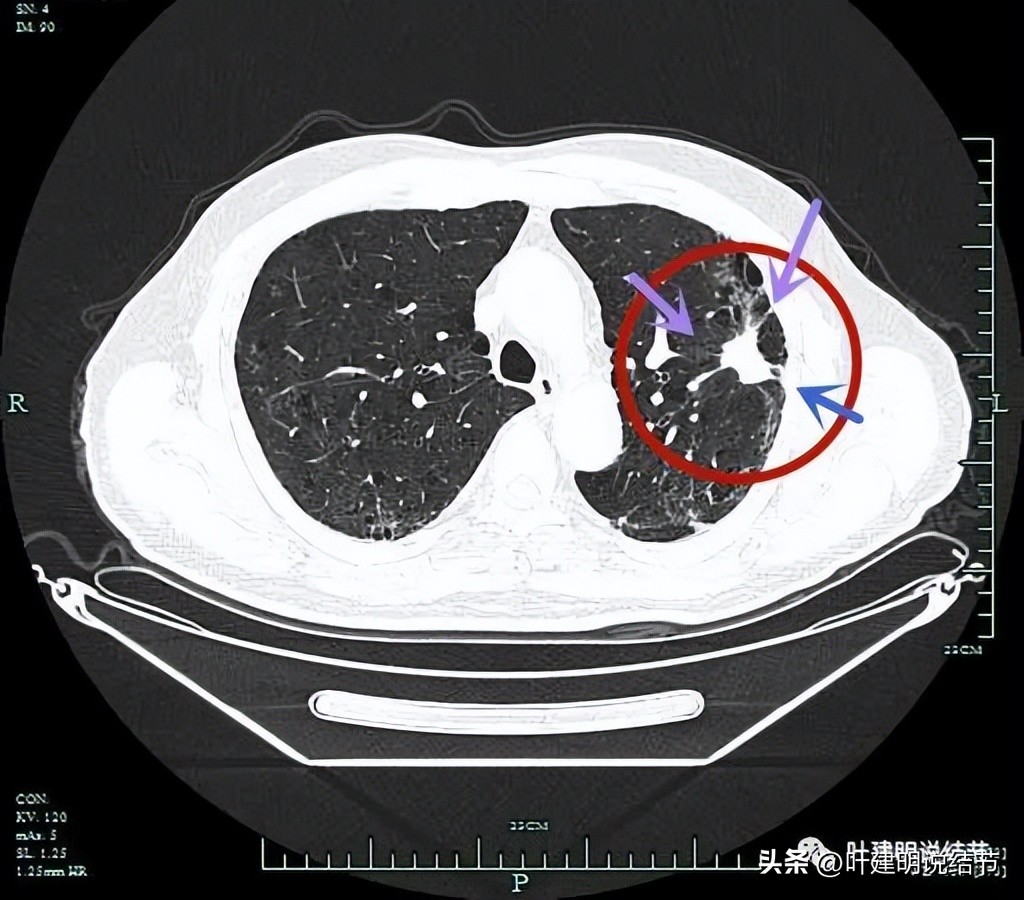

局部有细毛刺(紫色箭头)。

表面不平,分叶状。

病灶实性,有纠集感;有胸膜牵拉;有毛刺征;有血管征。

毛刺与牵拉。

靠前侧的连续细毛刺与不平,明显的恶性影像特点(紫色箭头)。